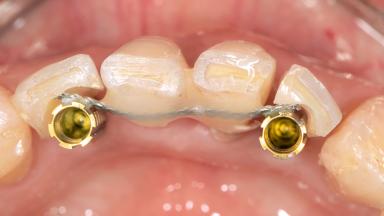

Immediate Replacement of Four Mandibular Anterior Teeth with a Conventionally Loaded Implant-Supported Fixed Dental Prosthesis

This case from German Gallucci, Adam Hamilton, and Teresa Chanting Sun details immediate placement with a conventional loading protocol (type 1C). It demonstrates a digital workflow combined with risk assessment to determine the best possible treatment approach for replacing mandibular anterior teeth.

A 63-year-old female patient was referred by a periodontist for consultation and assessment with regard to implant rehabilitation of the mandibular incisors. The patient presented in good health with no history of smoking or significant medical history. The patient’s chief complaint was mobility of the mandibular anterior dentition. She had a history of periodontal disease, which had been treated and followed by a periodontist with regular maintenance every four months over the previous ten years.